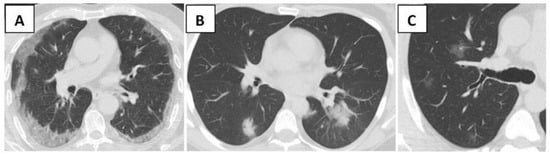

| Typical, n (%) | 316 (60.7) | 150 (48.5) | 166 (78.3) | <0.001 | |

| Bilateral, peripheral, and basal GGO with or without consolidation, n (%) | 301 (57.8) | 139 (45) | 162 (76.4) | <0.001 | |

| Multifocal rounded GGO with or without consolidation, n (%) | 25 (4.8) | 21 (6.8) | 4 (1.9) | 0.01 | |

| Crazy paving pattern, n (%) | 10 (1.9) | 0 (0) | 10 (4.7) | <0.001 | |

| Involved Lobes and global Score | |||||

| RUL, n (%) | 297 (57) | 132 (42.7) | 165 (77.8) | <0.001 | |

| RML, n (%) | 242 (46.4) | 98 (31.7) | 144 (67.9) | <0.001 | |

| RLL, n (%) | 250 (47.9) | 134 (43.3) | 170 (80) | <0.001 | |

| LUL, n (%) | 305 (58.5) | 129 (41.7) | 176 (83) | <0.001 | |

| LLL, n (%) | 299 (57.4) | 123 (39.8) | 176 (83) | <0.001 | |

| Global score, median (IQR) | 5 (0–10) | 1 (0–6) | 10 (5–13) | <0.001 | |